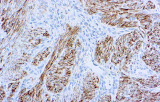

- Assegnazione del lignaggio & principali diagnosi differenziali: Fenotipizzazione cellule B vs cellule T (es. CD20 vs CD3), supportata da fattori di trascrizione nucleari delle cellule B come PAX5 quando i marcatori pan-B sono deboli/assenti.

- Pannelli orientati alle entità per neoplasie linfoidi:

- LLC/LLS: co-espressione caratteristica di CD5 e CD23 nelle cellule B CD20+ (l'interpretazione richiede consapevolezza del pattern perché sono presenti cellule T reattive).